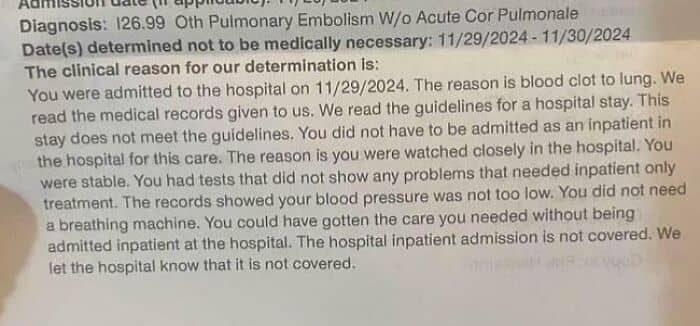

#5 United Healthcare Denial Reasons